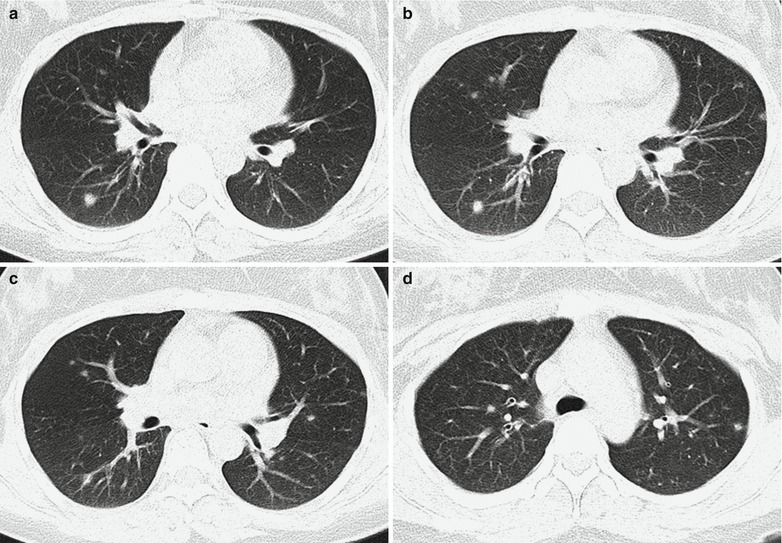

CT Scanning

CT scanning demonstrates pulmonary consolidation, thickened bronchial vascular bundles, ground-glass opacity, lesions at the lobular center, and nodular shadows (Figs. 23.18 and 23.19). In rare cases, cords like shadow can be demonstrated, with accompanying pleural effusion.

Fig. 23.20.

Adult measles complicated by pneumonia. (a–d) Plain CT scanning demonstrates multiple nodular shadows with different size in both lungs (Note: The case and the figures were provided by Wu JP and Yun J from the Third People’s Hospital, Changzhou, Jiangsu, China)